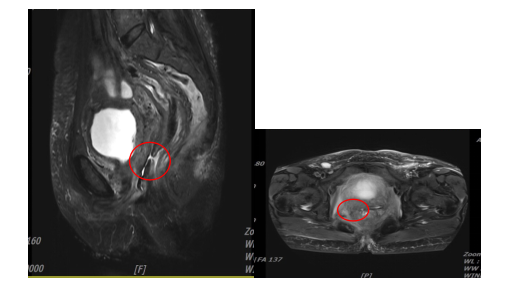

盆腔MRI提示:阴道肿瘤侵犯直肠

MRI:病变直径缩小1cm,肿瘤体积减少约50%